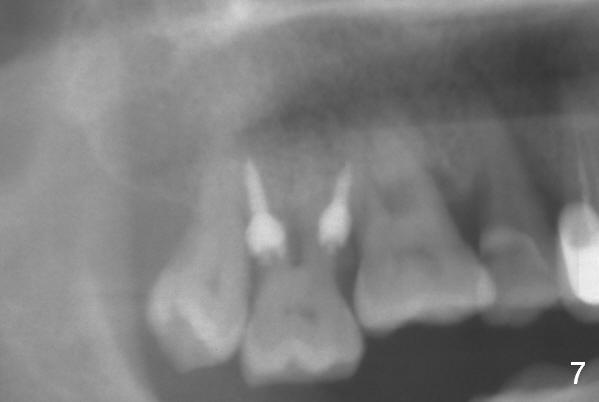

Two days post #31 implant placement, the patient returns for orthodontic intrusion of the tooth #2 with mini-implants (Fig.1). The palatal cusps have been trimmed (Fig.2 ^), since they almost contact a healing abutment at #31(*, Fig.3). Two mini-implants are to be placed mesiobuccal and distopalatal to the affected tooth. After minimal injection of Lidocaine, a 1.6x6 mm Tomas implant is placed in full length mesially (Fig.4), while the other (1.6x8 mm) half way (Fig.4). Following change in implant site mesially (Fig.6 >), the implant is half inserted (Fig.5). It appears that the tip of the distal implant is toward the tooth #1 (Fig.5). After withdrawing the implant partially, it is re-directed to apparently ideal trajectory (Fig.7). Ideally the mesial implant (Fig.8) should have been placed partially initially (Fig.4,5,7) so that the trajectory could have been able to be changed.

The buccal implant becomes loose in 2-3 months. When the wound heals (Fig.9 <), a 1.6x`10 mm implant is placed with the help of PAs for trajectory (Fig.10,11) and in the nonkeratinized gingiva (higher, the crestal bone may have been traumatized by previous implant placement, Fig.12). Two months later, the tooth #2 is partially intruded (Fig.13). A provisional (Fig.14 P) is fabricated in the osteointegrated implant at #31 with supraocclusion so that the remaining dentition has no occlusal contact (*). The periodontally compromised tooth #2 becomes in buccoversion in 2 months. The provisional is removed, while a lingual button is placed in the buccal surface of the tooth #2 (Fig.15). With power chain attached to the lingual mini-implant, the tooth #2 is lingualized in 2 months. The provisional and the implants are reused for final intrusion (Fig.16). The treatment is nearly 11 months. The buccal implant, although placed in the movable mucosa, remains stable and healthy (Fig.17). The tooth #1, as a guiding plane (to prevent #2 from distalization during intrusion), is not extracted after intrusion is completed.